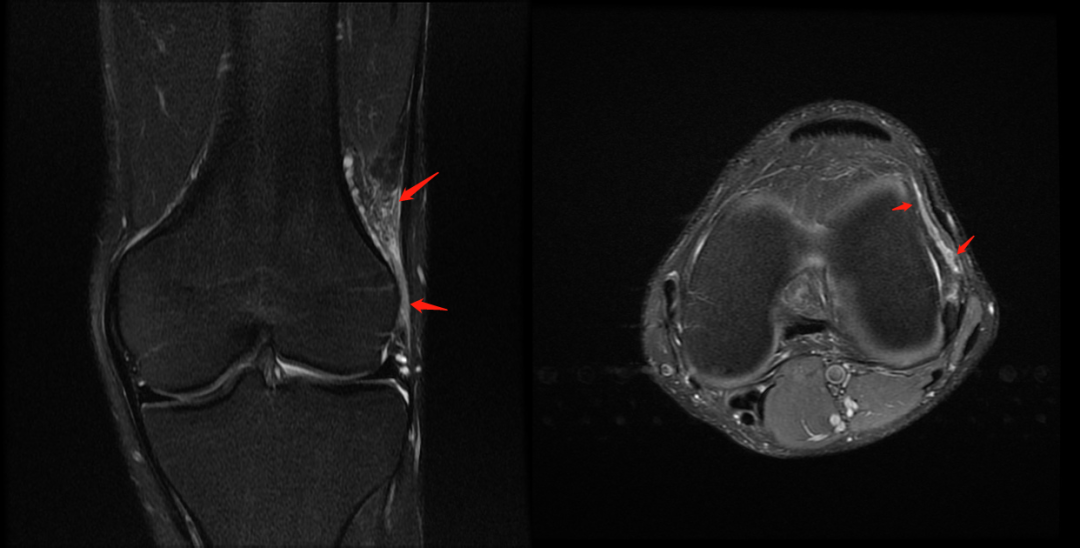

主诉:右膝关节外侧反复疼痛不适半年余,近一个星期疼痛加重。现病史:患者右膝关节外侧间歇性疼痛不适半年余,近一个星期疼痛加重,屈膝时明显,门诊行膝关节 X 线片检查,未见明显异常。患者否认手术史/外伤史。为进一步明确情况,我们建议患者行膝关节磁共振检查;图像如下:T1

T2 压脂

冠状位

轴位

大家是否发现什么异常?该患者是膝外侧疼痛不适的症状,我们重点观察了外侧半月板及外侧副韧带,但是我们发现是正常的;

但是我们发现有一个地方信号不对;

大家发现了没有?那这是什么呢?

那么我们刚刚看到信号增高的就是髂胫束,排除了半月板和外侧副韧带的问题,那么膝关节外侧疼痛是不是这个原因导致的呢?